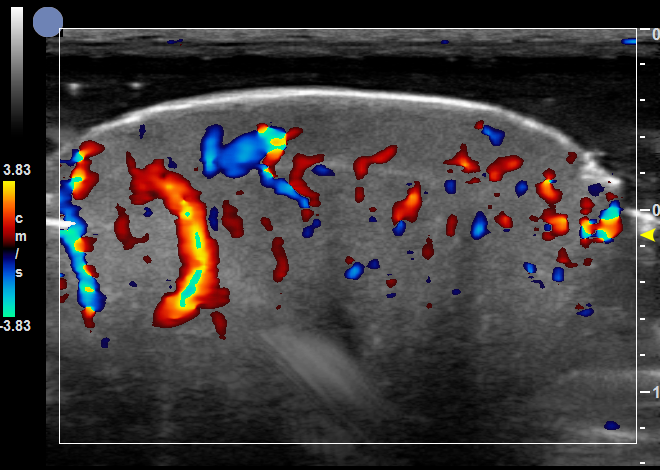

增殖期血管瘤